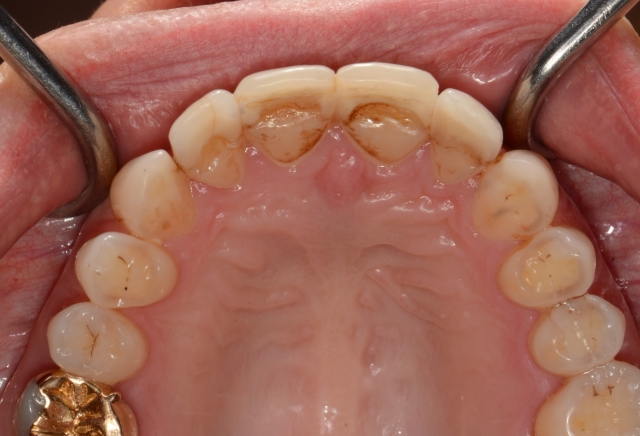

I also noted that tooth wear was not distributed evenly on the dentition. The lingual aspect of the maxillary anterior teeth looked severely worn.

I pulled out the leaf gauge to confirmed the joints could be loaded, and began progressively decreasing the number of leaves to discover the first point of contact at the seated condylar position. I discovered a posterior initial contact at a significantly open position that deflected the mandible so the mandibular anterior teeth ran into the lingual aspect of the anterior teeth at the very place where her veneers had been breaking.

We mounted diagnostic casts in centric relation based on a leaf-gauge bite registration before the first point of contact, confirmed the same posterior initial contact and shift we saw in the mouth, and waxed up a new occlusion by making changes that created coincidence between the seated condylar position and maximum intercuspal tooth contact. These changes provided for space in the anterior to create appropriate form and smooth function.